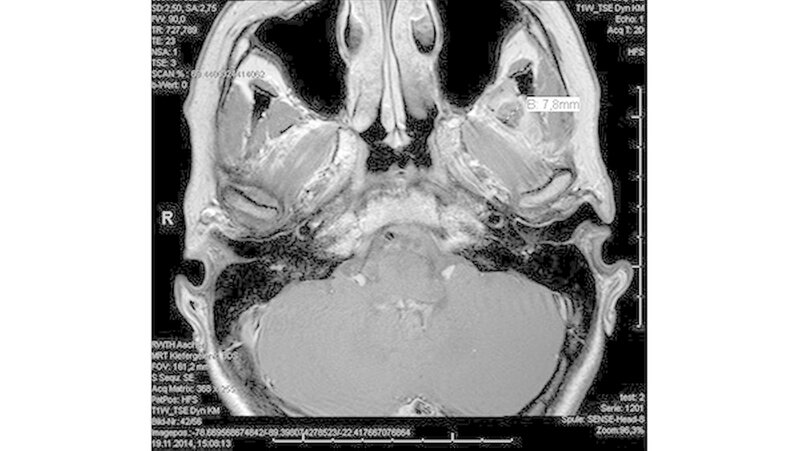

Das neun Tage später durchgeführte MRT zeigte keinen Anhalt für eine Läsion des Diskuskomplexes beidseits. Es wurde jedoch eine umschriebene, teils T2-hyperintense sowie kräftig randständig kontrastmittelaufnehmende Läsion im M. pterygoideus medialis links (axial bis zirka 1,0 cm) angrenzend an den Processus muscularis vereinbar mit einem kleinen intramuskulären Abszess beschrieben (Abbildungen 3 a und b).

Des Weiteren erschien der M. pterygoideus medialis links in seinem ganzen Verlauf ödematös verändert, jedoch ohne Anhalt für eine Beteiligung der umliegenden Strukturen wie dem M. pterygoideus lateralis.